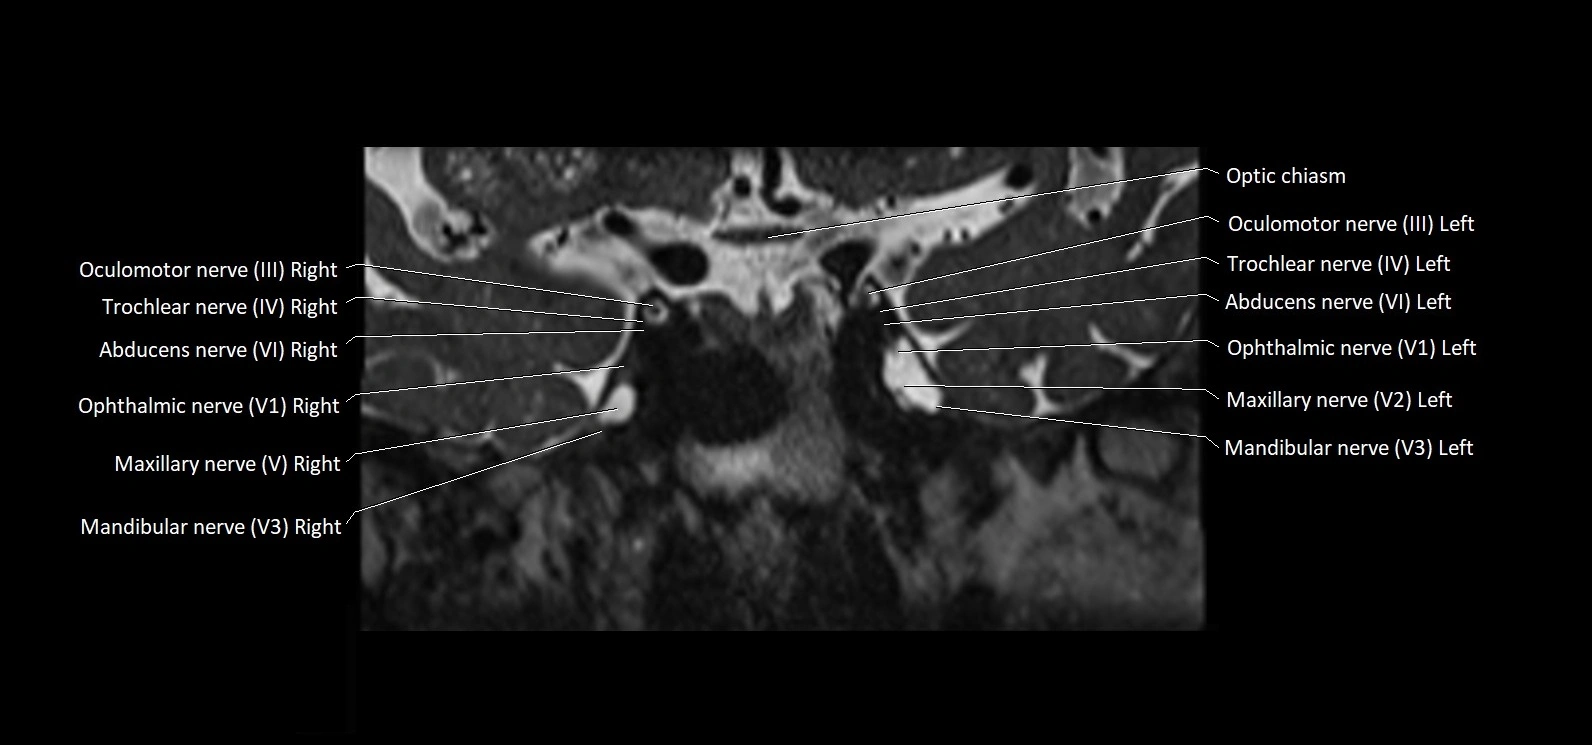

MRI Appearance

• The abducens nerve is a small, thin, linear structure

• Best visualized on high-resolution T2-weighted 3D MRI sequences (e.g., FIESTA or CISS)

• Seen as a hypointense (dark) line running from the brainstem at the pontomedullary junction, traversing the prepontine cistern, and entering Dorello’s canal under the petrosphenoidal ligament, then into the cavernous sinus, and finally the orbit

• May be challenging to visualize in standard MRI due to its small size

• Pathology may be inferred by absence, displacement, or enhancement of the nerve

MRI images

image